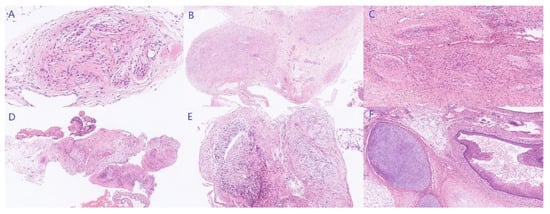

A suspected diagnosis of GTS was established, and an exploratory laparotomy was performed on April 2022. An 8-cm solid cystic mass with a smooth appearance and multiple nodular protuberances originating from the pouch of Douglas was found during the operation. There were no abnormalities in either adnexa, except for a 1-cm endometrioma on the right ovary, and there was no connection between the bilateral ovaries and the pelvic mass. There was extensive seeding of glial-like nodules in the uterine serosa, vesical peritoneal reflection, right pelvic wall peritoneum, and partial omentum majus (Figure 4). Intact mass removal, partial uterine serosa and peritoneal resection, and partial omentectomy were conducted. The tumor showed a smooth and irregularly lobulated gross appearance (Figure 5). The cross-sectional profile of the mass showed lipids and multiple calcified nodules without necrosis (Figure S1). Postoperative paraffin pathology showed a pure mature cystic teratoma in the pelvic mass without any immature components, and glioma was noted in the other resection samples, confirming the diagnosis of GTS with synchronous GP (Figure 6).

Figure 6. Pathology results of peritoneal seeding of GP and GTS (HE staining). Mature neuroglia presented with distinctive rounded, or ovoid nodules with well-defined boundaries involving omentum majus ((A), 200×), vesical peritoneal reflection ((B), 25×), peritoneum of ascending colon ((C), 50×), right ovarian cyst ((D), 50×), and posterior uterine wall ((E), 50×), while mature cartilage and squamous epithelium differentiation were observed in the mass ((F), 50×).